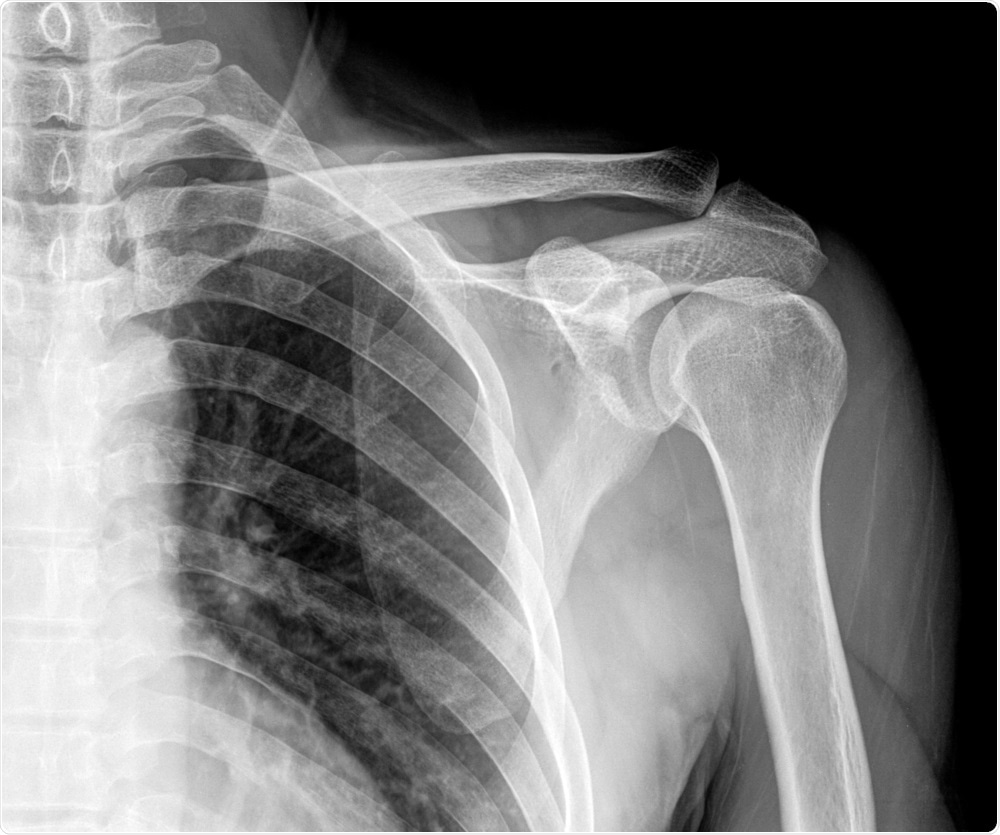

X-ray image of a broken shoulderImage Credit: Xray Computer / Shutterstock

The problem is that the human body is not a flat surface and within the human body there are variations in tissue density that can affect whether X-rays are stopped and how they are scattered.

When you try to image the inside of the human body, scattering and changes in the stopping power of X-rays can distort the image, leading to errors in diagnosis, for example fractures or tumor sites, that could affect the patient treatment down the line.

Imalka: The first thing would be that the clinicians would be able to diagnose where to deliver the x-ray dose more accurately. This would be useful in areas like cancer therapy and bone fracture imaging.

Using this technology, clinicians would not have to carry out any complex mathematical manipulations to identify precisely where the fractures are. Effectively it is allowing a more accurate diagnosis.